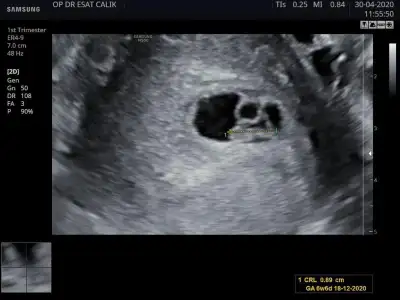

Bu da benim fasulyem. Normalde sata gore 7+6 ama ultrasonda 6 haftalik cikmis. Doktor kese kucuk cocuk normal kalbi durabilir dedi. Kanama alanim var fotoda belli oluyor zaten

Neden kalbi durabilirmiş Allah korusun Allah sağ salim sana kavuştursun